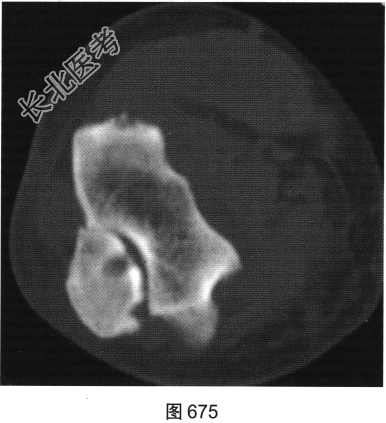

患者女性,62岁,右侧肘关节肿胀、疼痛1年余。肘关节正侧位X线片及CT检查见图673~图676。

- 多项选择题1.对该患者影像征象描述正确的是( )

A、关节腔积液

B、尺骨关节面囊状骨质破坏

C、肘关节面明显骨质增生硬化

D、肘关节软组织肿胀

E、尺骨近段骨膜反应

F、肘关节间隙变窄

G、骨质疏松